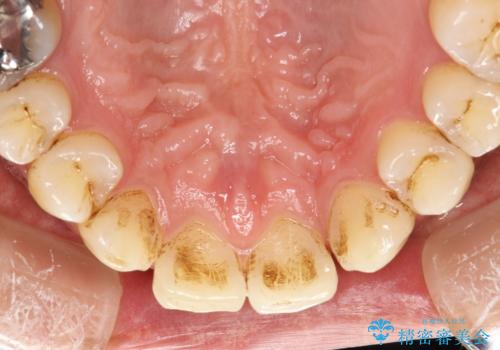

2年ぶりのクリーニング(PMTC)

ステインとプラークが内側外側にとても多く付いていました。

タバコも吸うそうで、ステインが多かったです。60分コースでもギリギリ終わるくらいの汚れの量だったため、定期的にクリーニングやメンテナンスを行うようにおすすめしました。